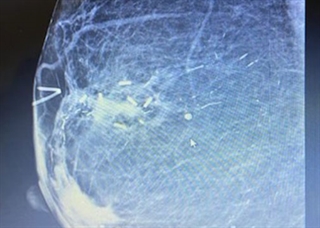

After a biopsy or tumor removal, the Accusyte fiducial sutures are sewn around the perimeter of the tumor bed at the anterior, posterior, middle, and lateral planes of the tumor cavity. The fiducials allow for accurate delineation of target volumes during treatment planning and assist with image guided radiation therapy (IGRT) before each session.

The fiducial markers are woven within an absorbable suture. When the body absorbs the suture, the fiducial markers remain within the tissue. Migration of the markers from their original position is unlikely, as the tissue produced during the healing process holds the markers in place. Sutures are sewn into place using the same technique as other sutures commonly used.

Disease site recommendations: Head & Neck, Breast, Lung, Abdomen, & Prostate.